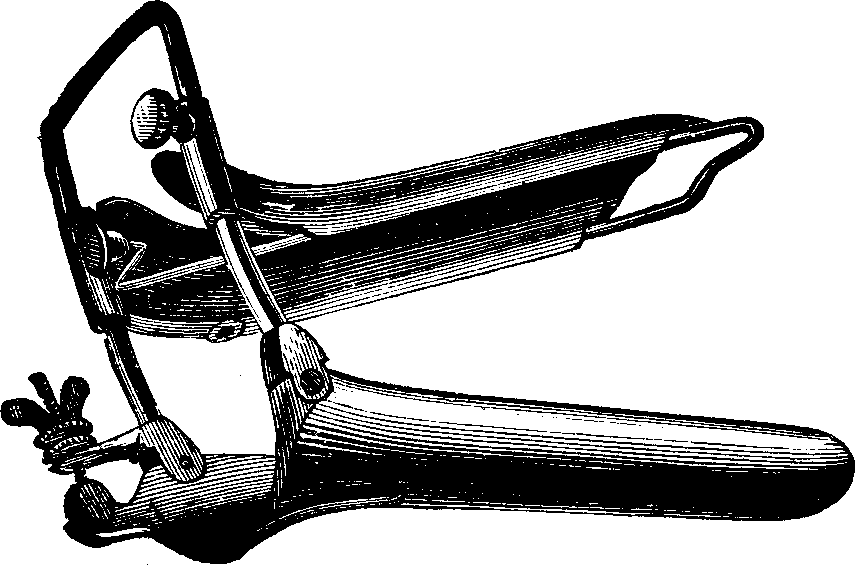

Fig. 3. THE UTERINE DILATOR. This instrument is introduced

into the canal of the uterine neck with its blades closed. By means of the

thumb-screw the blades are then separated as shown in this illustration,

the cervical canal being thereby dilated to the required extent.

Treatment. From the nature of this malady, it will readily be seen that no medical treatment can effect a radical cure. We must therefore resort to surgery. In a small proportion of cases, the stricture may be cured by repeated dilations of the constricted part of the cervical canal. This may be accomplished by using a very smooth probe which is fine at the point, but increases in size, so that its introduction will widen and expand the orifice and canal. The stricture may be overcome in many cases by using different sized probes. In some instances, we have employed the uterine dilator, represented by Fig. 3. We have also introduced sea-tangle and sponge tents into the neck of the womb, and allowed them to remain until they expanded by absorbing moisture from the surrounding tissues. The latter process is simple, and in many cases preferable. By means of a speculum (see Figs. 15 and 16), the mouth of the womb is brought into view, and the surgeon seizes a small tent with a pair of forceps and gently presses it into the neck of the womb, where it is left to expand and thus dilate the passage. If there seems to be a persistent disposition of the circular fibers of the cervix to contract, and thus close the canal, a surgical operation will be necessary to insure permanent relief. In performing this operation, we use a cutting instrument called the hysterotome (see Figs. 4 and 5). By the use of this instrument, the cervical canal is enlarged by an incision on either side. The operation is but slightly painful, and, in the hands of a competent surgeon, is perfectly safe. We have operated in a very large number of cases and have never known any alarming or dangerous symptoms to result. After the incision, a small roll of cotton, thoroughly saturated with glycerine, is applied to the incised parts, and a larger roll is introduced into the vagina. The second day after the operation, the cotton is removed, the edges of the wound separated by a uterine sound or probe, and a cotton tent introduced into the cervix, and allowed to remain, so that it will expand and thus open the wound to its full extent. This treatment must be thoroughly applied, and repeated every alternate day, until the incised parts are perfectly healed.

Fig. 4.

WHITE'S HYSTEROTOME. In operating, this instrument is introduced into the

canal of the neck of the womb, when a thumb screw in the end of the handle

is turned, by which a small blade is thrown out from each side, and as the

instrument is withdrawn from the canal an incision is made on each side,

thus enlarging the passage. The upper figure illustrates the instrument

closed, ready for introduction; the lower one, with the blades projected

for cutting.

Fig. 5. STOHLMAN'S HYSTEROTOME. This instrument has two cutting blades

which shut past each other, as seen in the lower figure, so as not to cut

when introduced into the canal of the uterine neck. After introduction, the

cutting blades are separated, as shown in the upper figure, the extent of

the incision being regulated by the thumb-screw attached to the handles, as

represented in the lower figure.